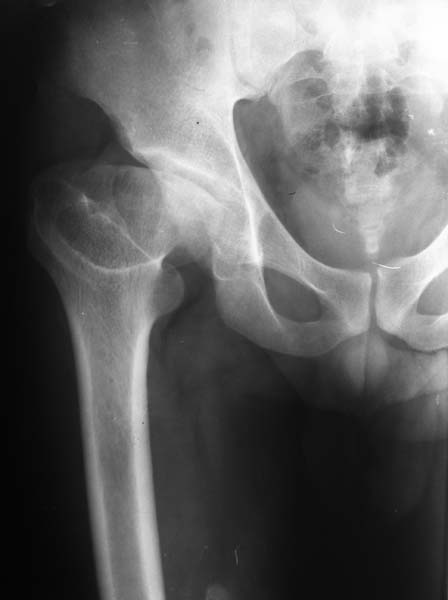

Больной, 24 года, спортсмен - борец вольного стиля, рост 170см, вес 92кг. Со слов была травма в детстве, но характер травмы описывает смутно и мед. документацию не предоставляет. Жалобы на периодические боли в области т/б сустава, но больше смущает укорочение конечности и хромота. Похоже на последствия остеохондропатии головки бедренной кости (Легга-Кальве-Пертеса) или неправильно консолидированного перелома. Объем движений в т/б суставе в пределах нормы, но по сравнению со здоровой ограничено: внутренняя ротация на 15гр., отведение до 25-30гр., наружняя ротация, сгибание, разгибание и приведение одинаково. Укорочение конечности 4.5см. Отмечается незначительная гипотрофия мышц бедра и голени: бедро в объеме меньше здорового на 5см, голень на 3см. Опыта ТЭТС при данной патологии у нас нет. Хотим отправить пациента за пределы республики. Больной к оперативному лечению морально и материально подготовлен)) При необходимости можно оформить квоту на ТЭТС.

Здесь комбинированная патология тазобедреннего сустава, связанная с высокостоящим вертелом и отсутствием (ротирована?) шейкой. А на стороне вертлужной впадины диспластический сустав. Обычно высоко расположенный вертел приводит к уменьшению силы мышц абдукторов, но отстутствие шейки привело к вертикальному расположению сил в суставе. Боли появляются из-за вертикального давления, а неровные контуры головки приводят к ограничению движений в суставе. Такое состояние быстро изнашивает сустав, и больные в молодом возрасте заканчивают тотальным протезированием.

Для оценки пригодности сустава надо сделать снимки во внутренной и наружной ротации, а также с отведением и приведением каждого сустава. Сравнительные снимки покажут возможный подвывих и укорочение, а также состояние суставной щели. 3D Компьютерная Томография покажет возможную ротацию шейки.

Снимок выполнен в прямой проекции с внутренней ротацией. На днях сделаем СКТ с 3D модуляцией.

Описался: рентгеновский снимок выполнен в прямой проекции с наружной ротацией.